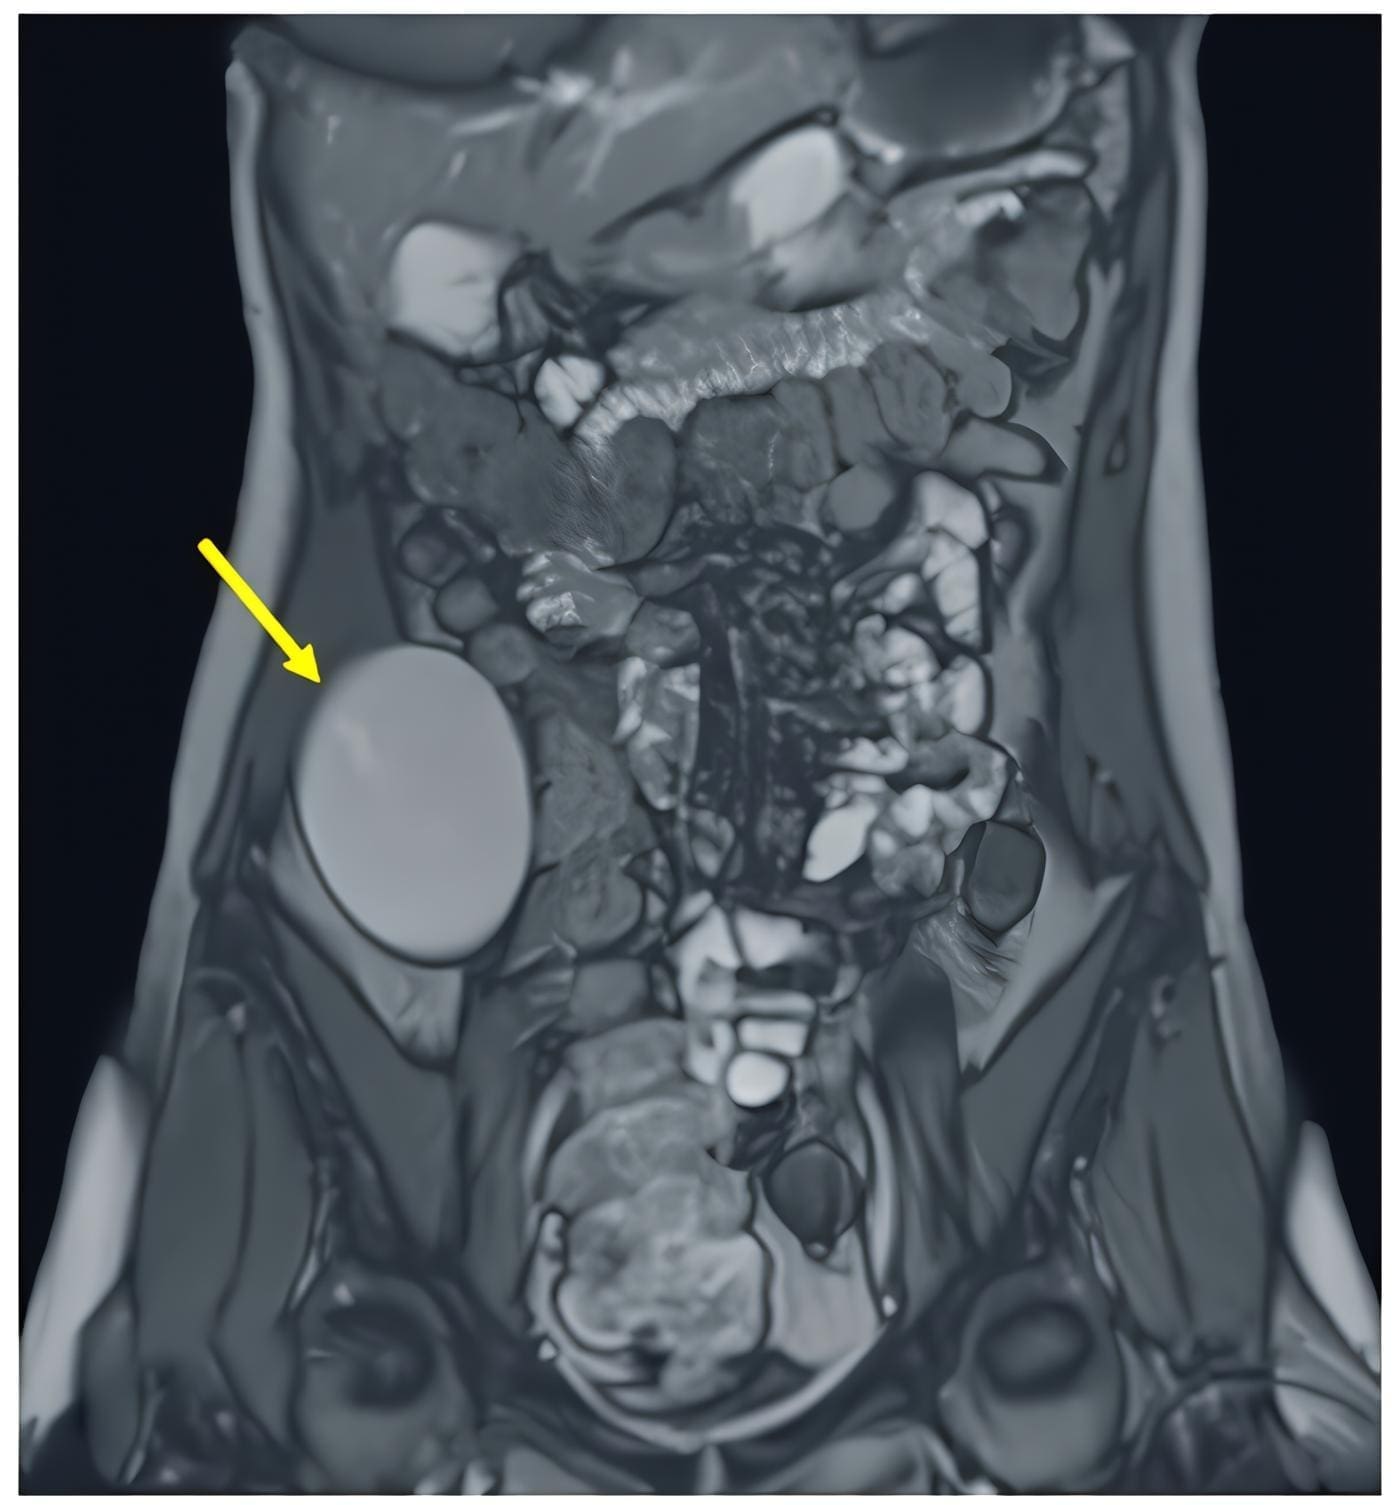

En la tomografía computarizada (figura 1) y en la resonancia magnética (figura 2) de abdomen se observó una lesión de densidad quística, de localización aparentemente extracompartimental en íntima relación con músculo transverso del abdomen derecho, que desplazaba el colon ascendente.

Figura 2. Resonancia magnética nuclear del abdomen con contraste (enteroRMN). En flanco y fosa iliaca derechos se identifica una formación quística unilocular (flecha amarilla) retroperitoneal (76 mm craneocaudal, 66 x 42 mm), sin componente infiltrativo, que determina discreto desplazamiento medial del colon ascendente en su tercio medio, localizándose inferior y alejada del riñón ipsilateral. Fuente: los autores.